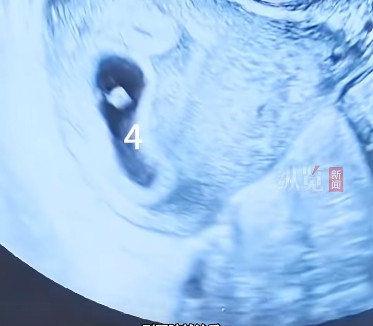

据媒体报谈,近日,江苏淮安的又名李女士(假名)因备孕繁重,自行在药店购买服用“多子丸”(促排卵药物),何况打针促排卵针。用药后其告捷怀胎,但早期产检露馅竟是四胞胎。

到病院就诊后,大夫以为四胞胎属于极高风险的多胎妊娠,若是不进行减胎责罚,胎儿流产、早产风险增多,重生儿面对极低体重、呼吸窘况、颅内出血等严重并发症,母体妊娠期高血压、糖尿病、贫血、产后大出血等发生率成倍增多。

大夫向李女士和家属释明:“保留四个胎儿,很可能一个王人活不好。医学上,单胎或双胎妊娠对母婴最为安全。”大夫捏行了孕早期减胎手术,减灭其中两个胚胎,易游娱乐告捷保留位置理思、发育精良的另外两个胚胎,手术历程胜利。